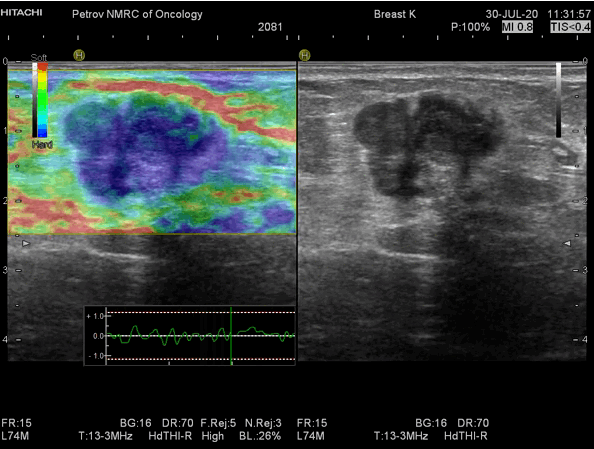

Эластография – инновационная ультразвуковая технология, ее еще называют ультразвуковой пальпацией. Известно, что рак молочной железы имеет более жесткую структуру, чем доброкачественные изменения. Именно эту характеристику и определяет эластография – она измеряет жесткость. Когда врач проводит вам эластографическое исследование – жесткие, а значит подозрительные образования, окрашиваются синим цветом, а эластичные (доброкачественные) – зеленым и желтым. Эластография порой имеет решающее значение.

Рис.10 Эластограмма эластичного образования – фиброаденомы молочной железы

Рис.11 Эластограмма жесткого образования – рака молочной железы